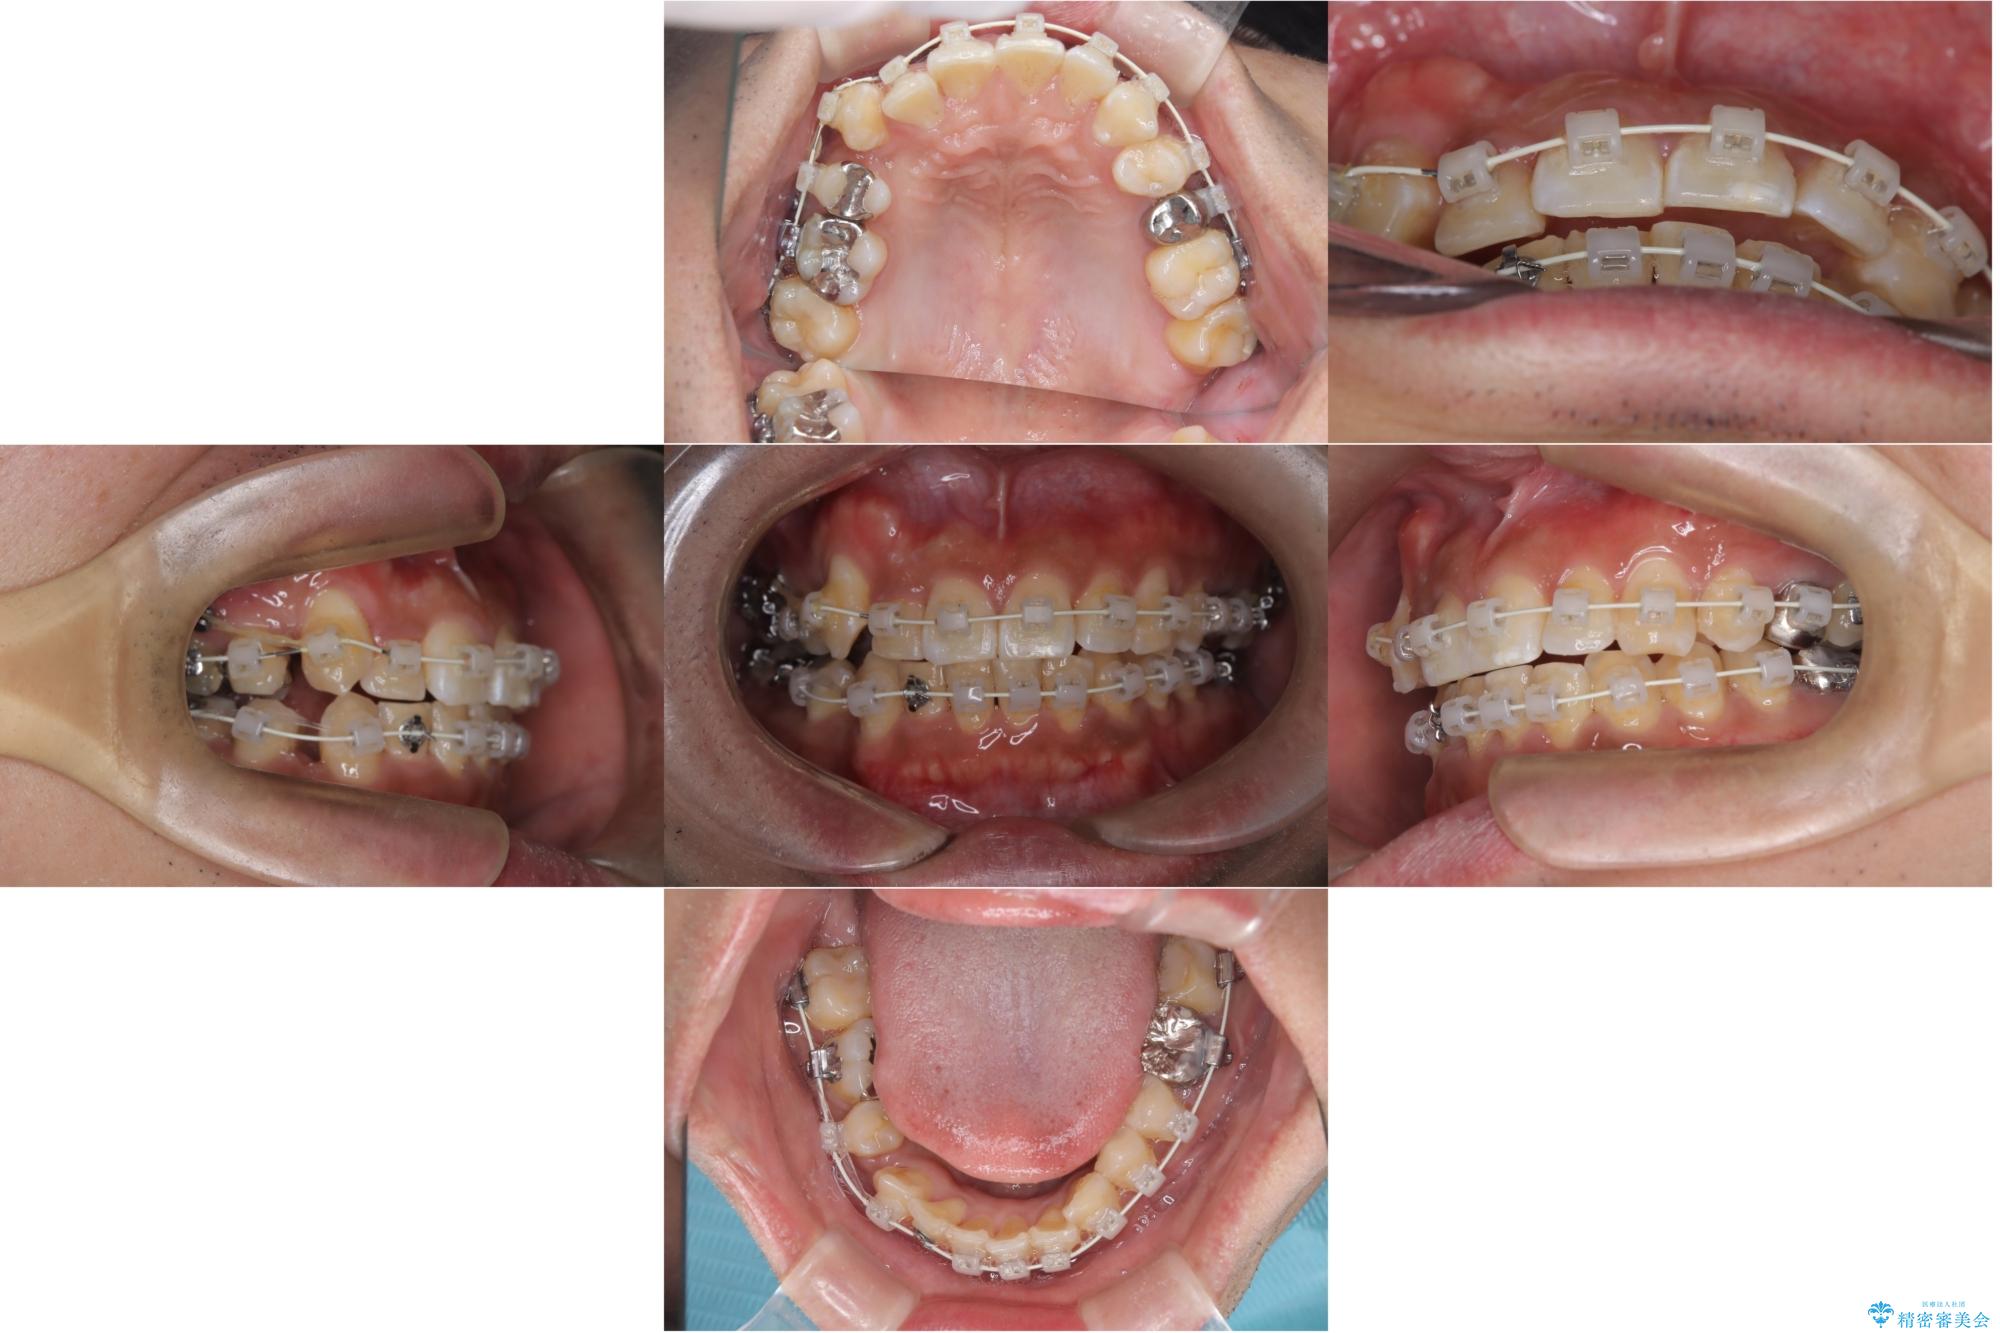

- ワイヤー矯正装置(審美装置)

右側2級、左側1関係だったため、右側上下第一小臼歯を抜歯し、ワイヤー矯正を行いました。

期間:2年6カ月